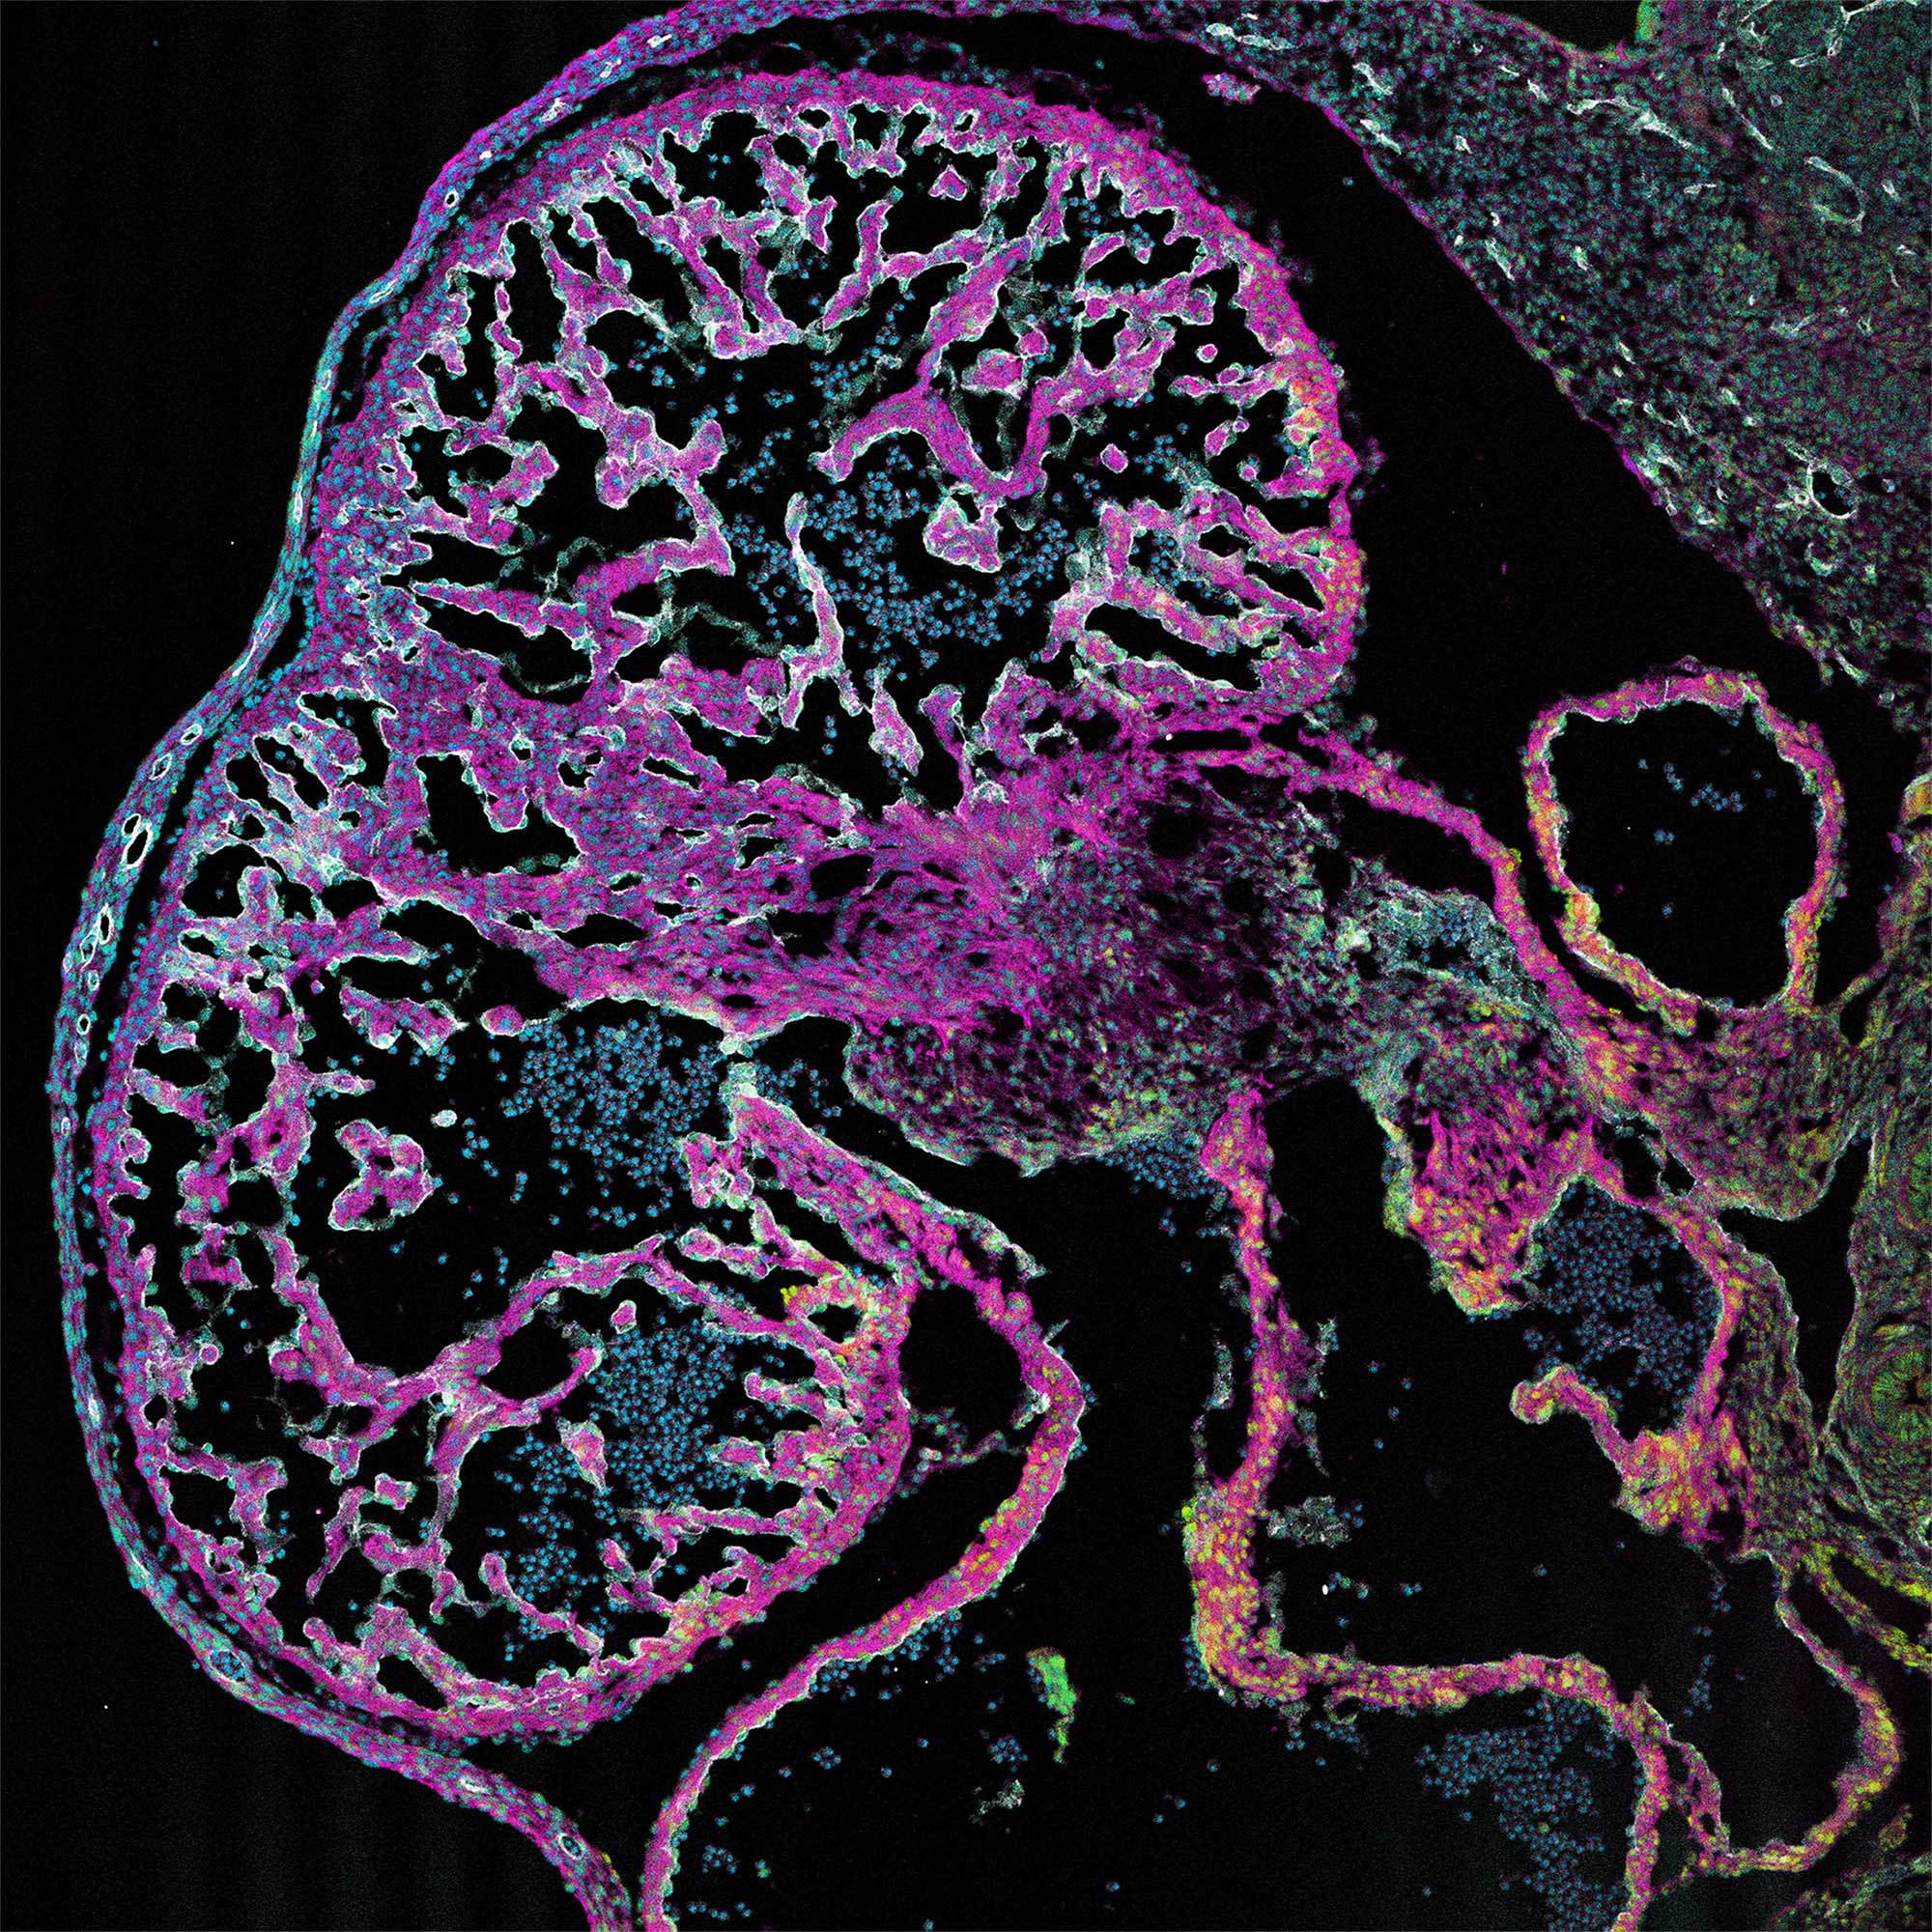

Lindsey (Avery) Fitzsimons '10, is a 5th year PhD student in Biomedical Science at the University of Maine, where she is currently working to complete her doctoral dissertation exploring the cellular disease processes involved in congenital heart disease/congenital heart defects. Lindsey began her tenure at Skidmore as a Studio Art/Art History major, but quickly became fascinated by the mysterious processes going on underneath the skin of the human body. Lindsey graduate from Skidmore with her B.S. in Health and Exercise Sciences, went on to complete a Master of Science degree in Clinical Exercise Physiology, and has spent the past 7 years working in various national and international biomedical research labs. Although she is committed to a career as a research scientist, Lindsey has continued to integrate her love for the visual arts through fluorescence microscopy, where she uses an experimental method called immunohistochemistry (immunofluorescence) to target specific proteins of interest by tagging them with specific fluorescent proteins (fluorophores) and imaging them using a specialized method of laser-microscopy , termed confocal microscopy (Leica Biosystems). Lindsey's images depict various stages of embryonic heart development (in mouse), and highlight different molecular targets critical to many of these developmental processes. IN addition to her research and teaching medical students at the University of New England College of Osteopathic Medicine (Biddeford, ME), Lindsey is passionate about communicating her science through her Instagram account (LAF_in_the_LAB), where she showcases many of her images to advocate for women, girls and moms in Science, Technology, Engineering, Art and Mathematics (STEM/STEAM).

The Developing Endocardium: (2D/10X) Confocal microscopy of the embryonic mouse heart at embryonic timepoint E12.5

Immunohistochemical analysis using primary clonal antibodies and secondary fluorophores